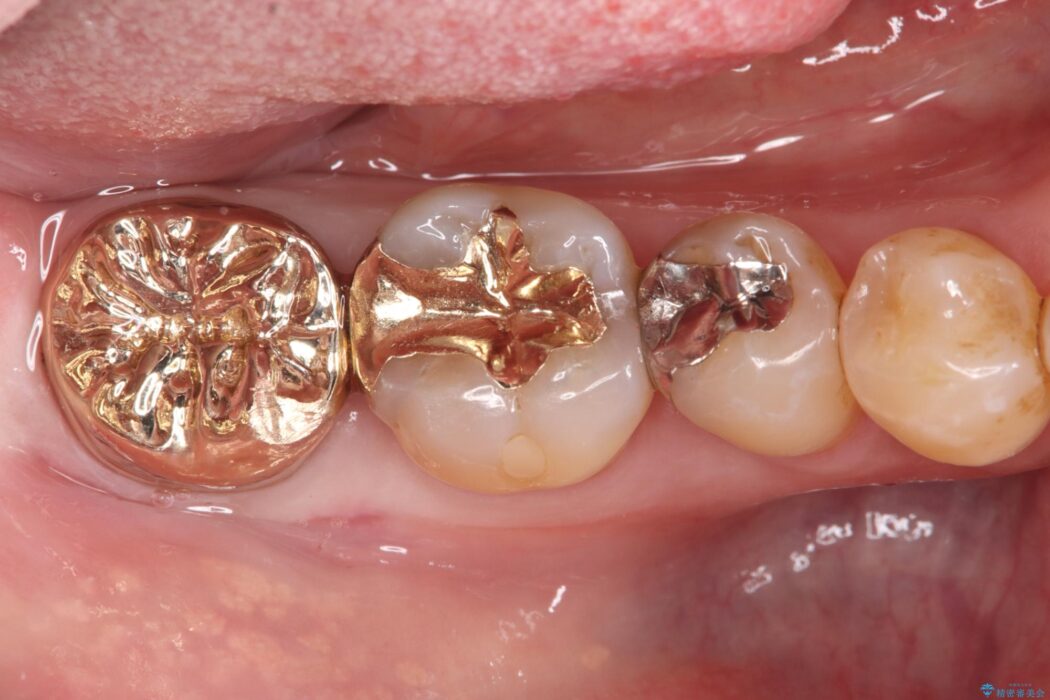

欠けた奥歯を土台から整え、金主成分の「PGAクラウン」で修復しました。PGAクラウンは、金を主成分とする合金でできており、非常に優れた特性を持っています。

欠けてしまった歯の構造的な弱点が解消され、患者様は硬いものでもしっかりと噛める、安心で機能的な奥歯を取り戻すことができました。